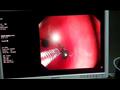

نجح فريق طبي في مستشفى الأطفال الجامعي التابعة لجامعة المنصورة، من استخراج "دبوس" من معدة طفل ابتلعه منذ نحو أسبوعين وتسبب في آلام داخل البطن.

أجرى الجراحة فريق طبي برئاسة الدكتور طارق بركات، والفريق المعاون من الجراحين وأطباء التخدير والتمريض.

من جانبه أكد الدكتور أحمد الرفاعي، مدير مستشفى الأطفال، أنه جرى استقبال الطفلة التي تبلغ من العمر 9 سنوات، بعد أن ابتلعت "دبوس" منذ أسبوعين، وبالكشف الطبي عليها تبين أن الدبوس اخترق جدار المعدة.